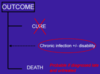

In terms of infection model, outline the possible outcomes for a patient with HIV